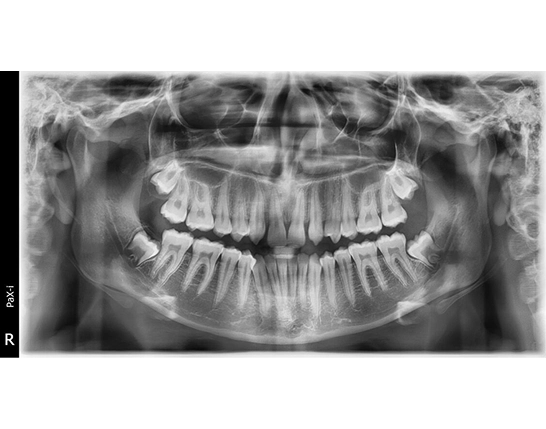

Based on her dental history and radiographic findings, I diagnosed that she was congenitally missing the upper lateral incisors (see Figure 2).